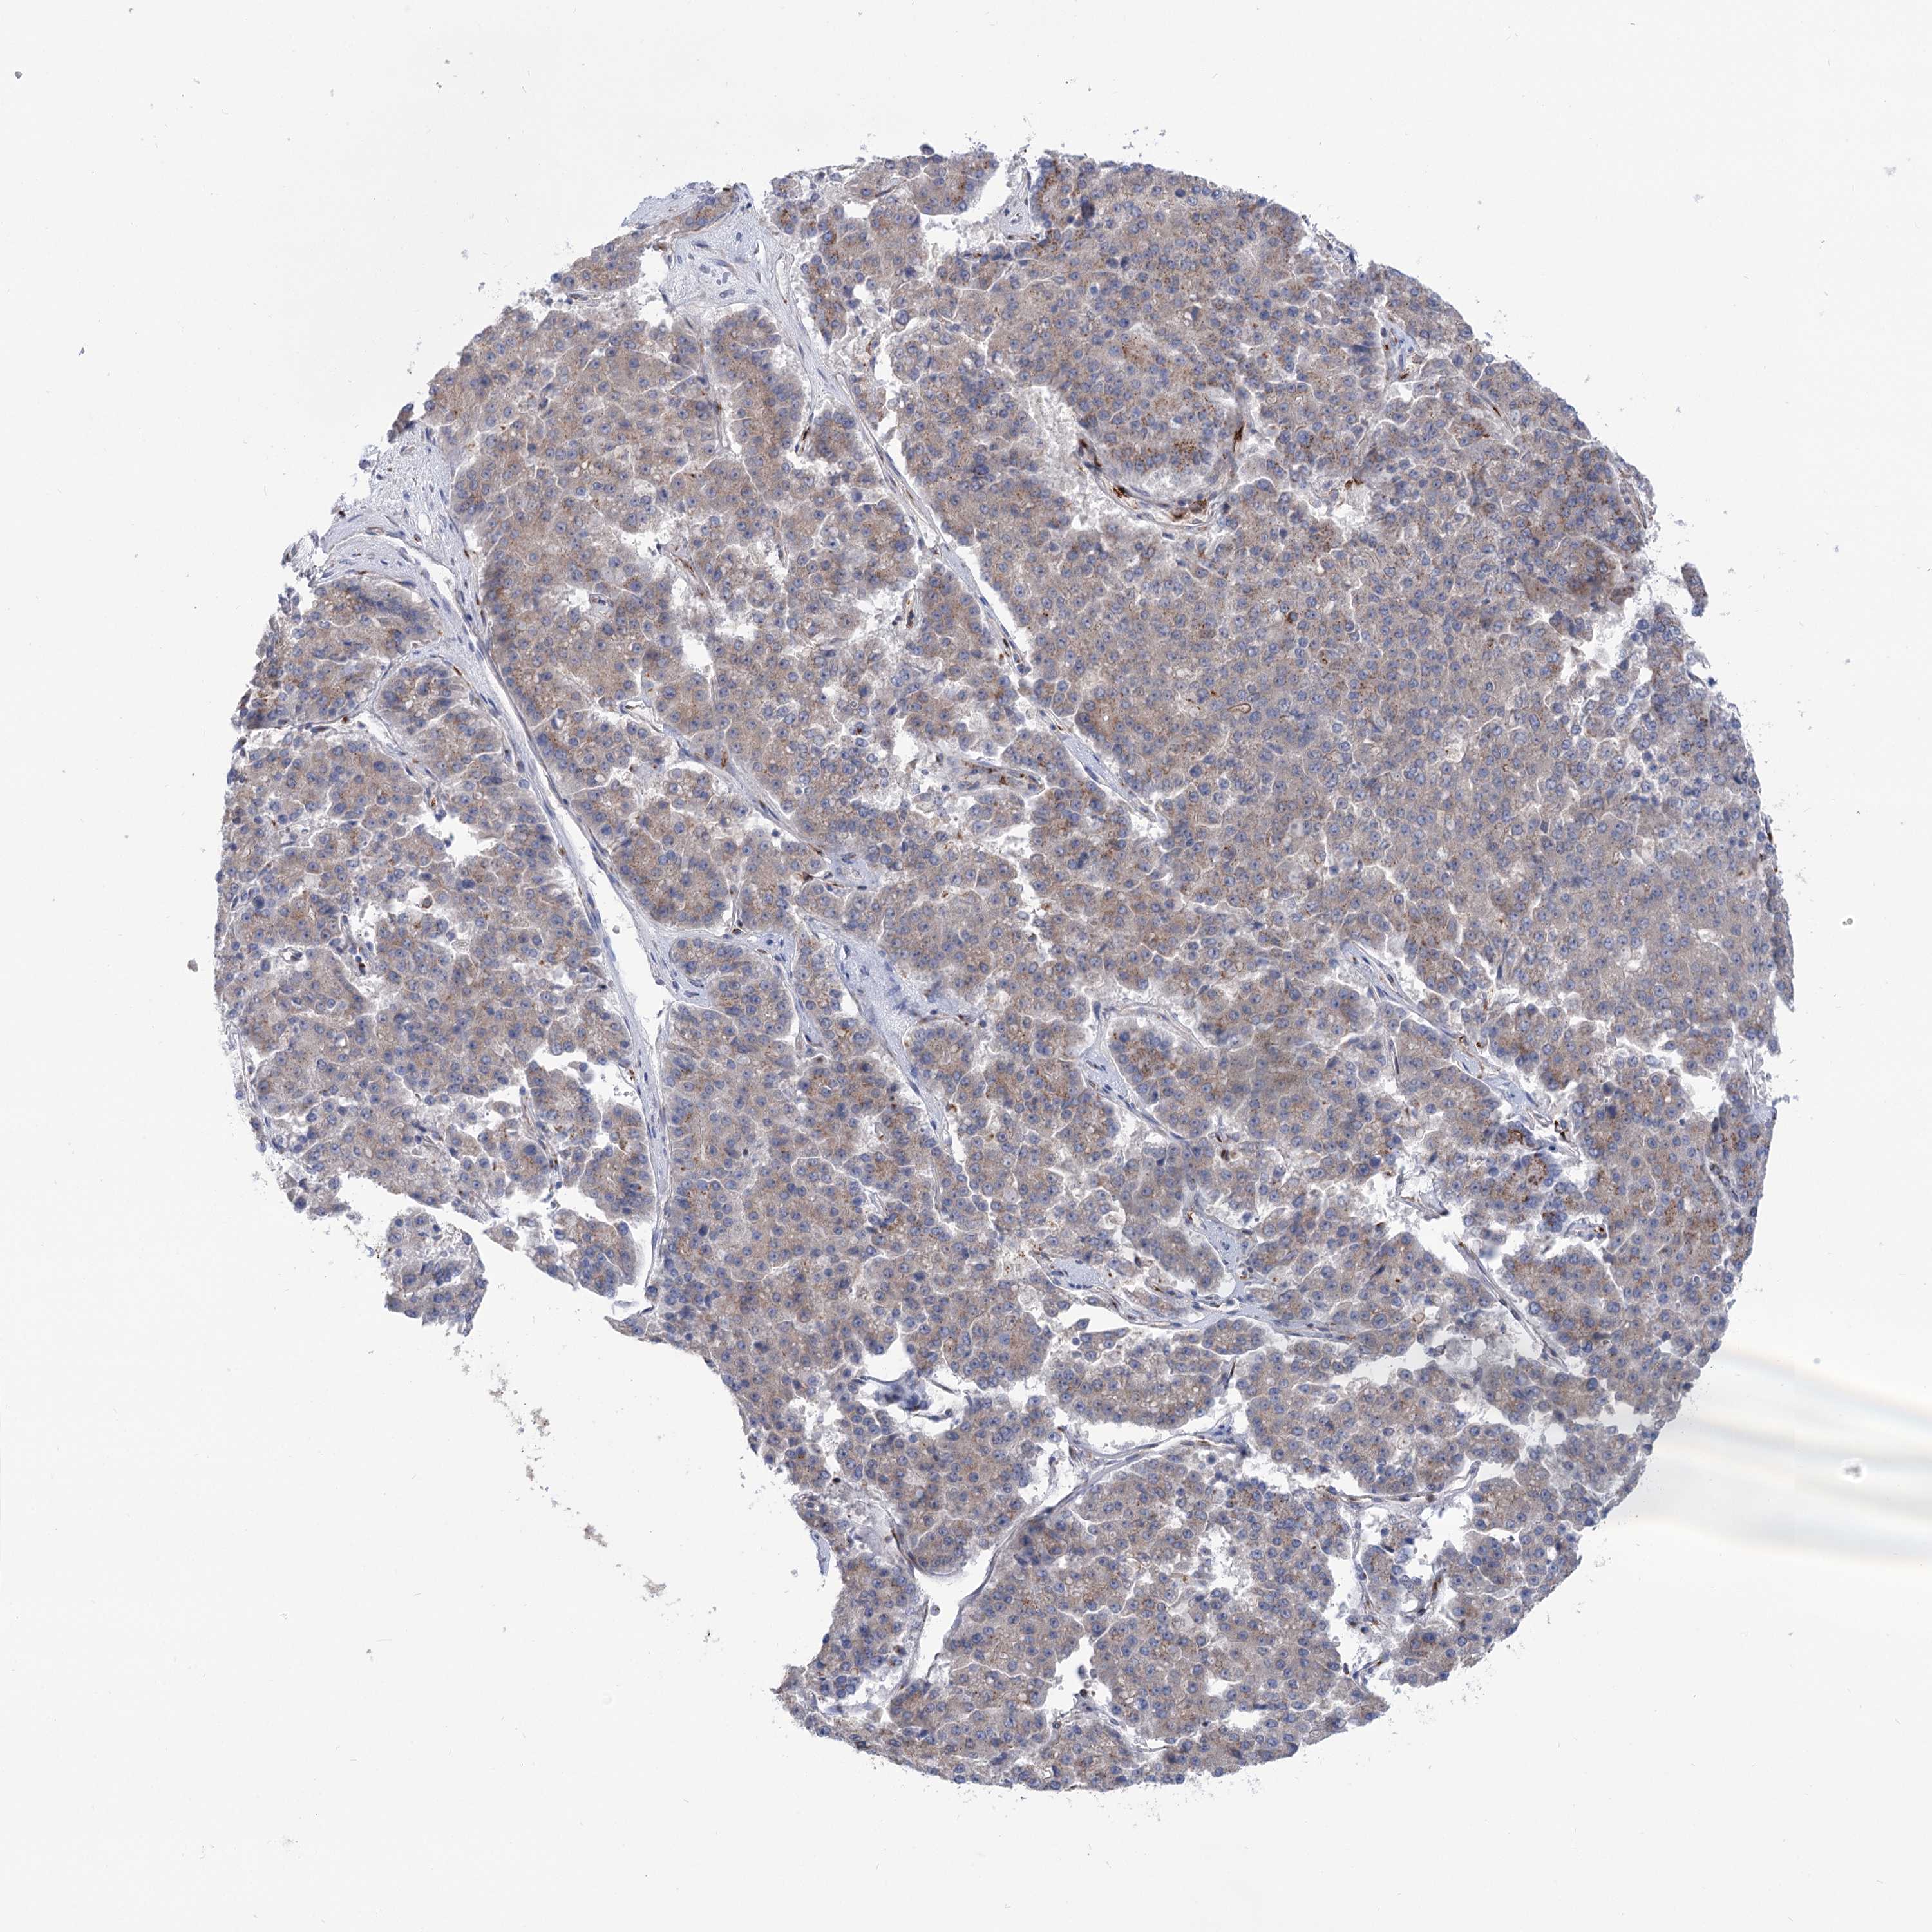

PANCREATIC CANCER - Protein expressioni

A mouse-over function shows sample information and annotation data. Click on an image to view it in a full screen mode. Samples can be filtered based on level of antibody staining by selecting one or several of the following categories: high, medium, low and not detected. The assay and annotation is described here.

Note that samples used for immunohistochemistry by the Human Protein Atlas do not correspond to samples in the TCGA dataset.

Antibody stainingi

Antibody staining in the annotated cell types in the current human tissue is reported as not detected, low, medium, or high, based on conventional immunohistochemistry profiling in selected tissues. This score is based on the combination of the staining intensity and fraction of stained cells.

Each image is clickable and will lead to virtual microscopy that enables deeper exploration of all samples and also displays staining intensity scores, fraction scores and subcellular localization as well as patient and tissue information for each sample.

Antibody HPA038299

Staining

High

Medium

Low

Not detected

Intensity

Strong

Moderate

Weak

Negative

Quantity

>75%

75%-25%

<25%

None

Location

Nuclear

Cytoplasmic/membranous

Cytoplasmic/membranous,nuclear

Adenocarcinoma, NOS